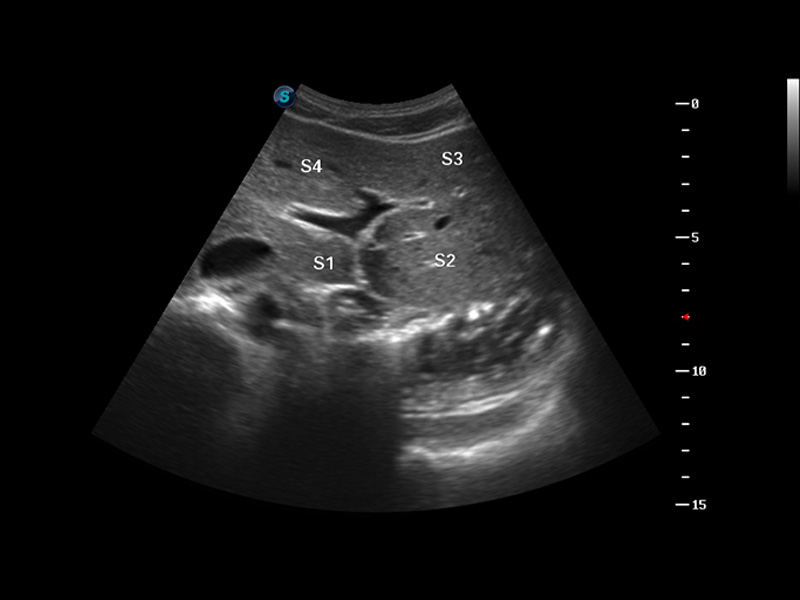

S8 EXP便携式彩色多普勒超声诊断仪是亚星官网研发的高端全身应用型便携彩超。高通道的VIS平台融合可视化(Visual)、智能化(Intelligent)和人性化(Smart)的特点,配以亚星官网自主研发生产的探头大家族,使您能够快速、准确的获得病人信息,提高工作效率的同时减轻疲劳。

3D/4D成像